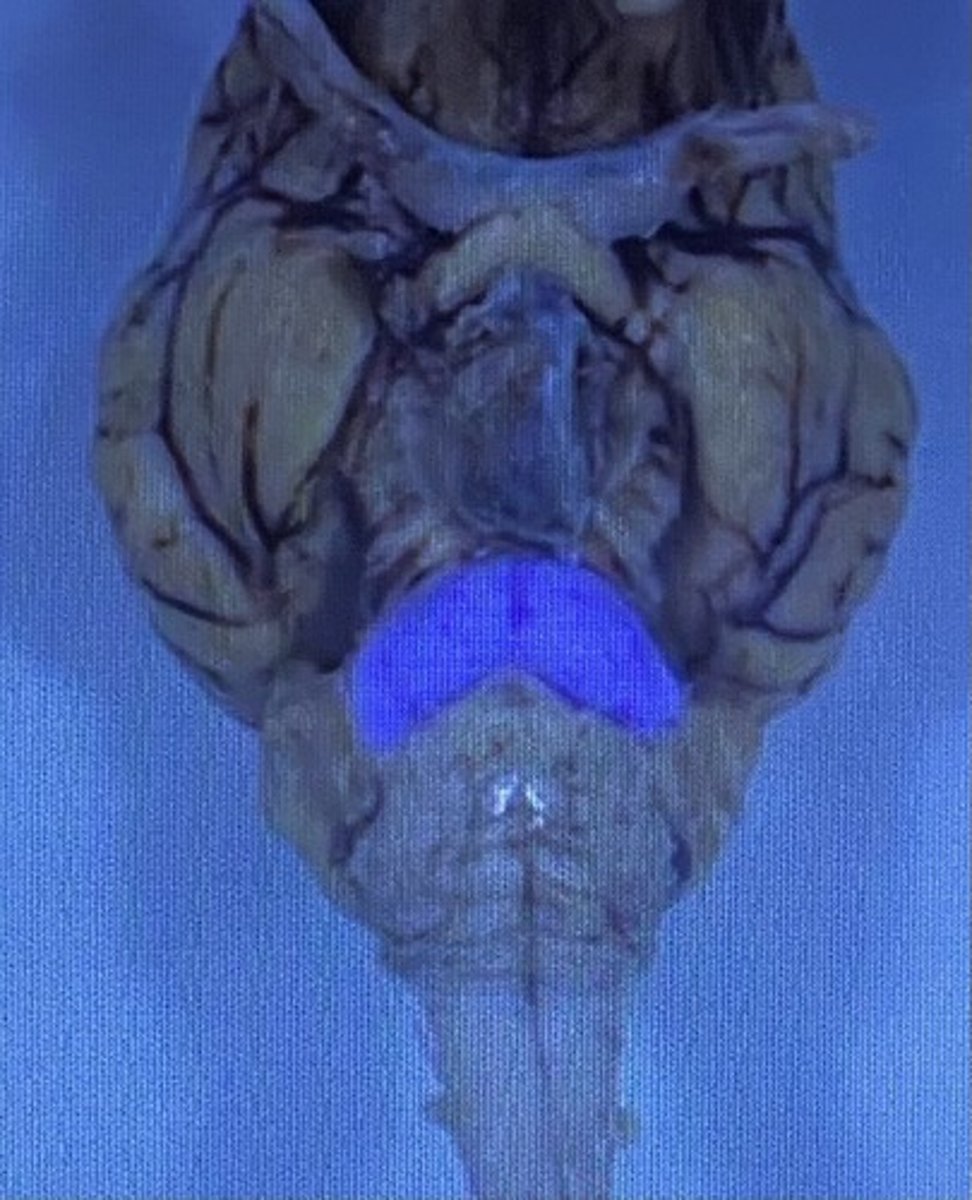

Cerebellum

Cerebellum

-coordinates muscles movements, muscle memory

Inferior Colliculi

-auditory reflexes

Superior Colliculi

-visual reflexes

Sheep Cerebellum

sheep 4th ventricle